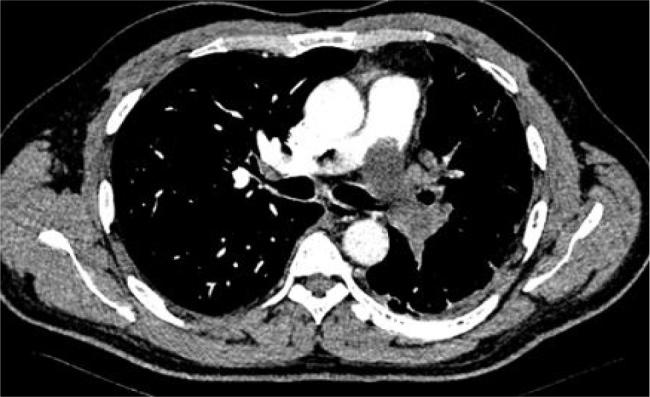

Deep vein thrombosis and pulmonary embolism (PE) are the third most common cardiovascular condition. Pulmonary artery intimal sarcoma (PAIS) is a rare tumour and is often misdiagnosed as a PE. This case report presents a 50-year-old man with fever, dyspnoea, cough and thoracic pain since a month. The patient had a history of two PE episodes. After diagnostic screening for tumour, including laboratory parameters, transthoracic echocardiography, computed tomography scan and positron emission tomography-computed tomography scan, PAIS was diagnosed. Unexplained recurrent PE should raise suspicion of a tumour or PAIS.

Recurrent pulmonary embolism should raise suspicion for tumours.Imaging and histopathology play a crucial role in diagnosis of pulmonary artery intimal sarcoma.Surgical resection as the primary treatment for pulmonary artery intimal sarcoma.